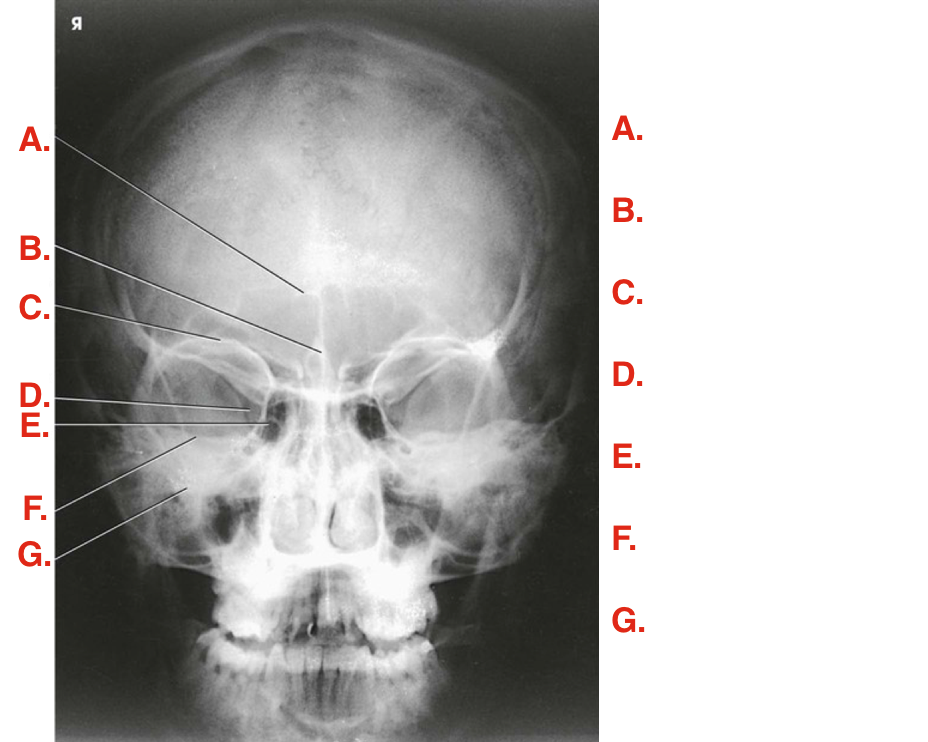

Question 5

Question

Label the image

Image:

3e77bc7a-aa20-4cca-8dd4-fbf2f993a691 (image/png)

Answer

parietal bone

occipital bone

frontal bone

foramen magnum

petrous ridge

posterior clinoid process

dorsum sellae